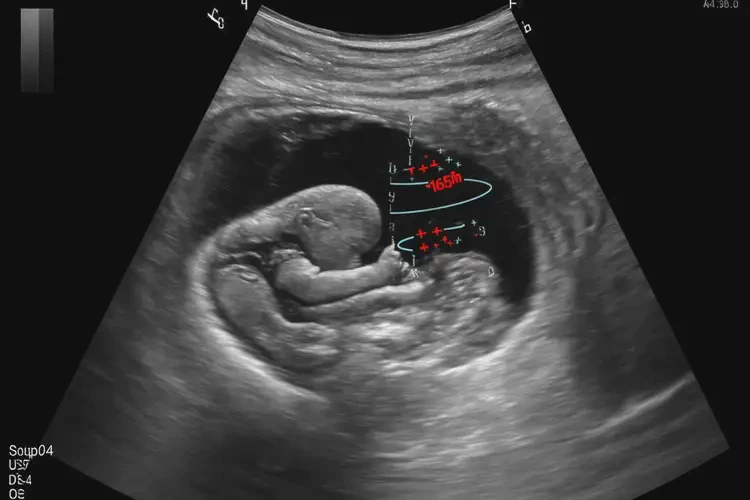

懷孕8個(gè)月胎心率165寶寶還能要嗎

胎心率165次/分鐘在懷孕8個(gè)月屬于正常范圍,寶寶可以要。

胎心率是指胎兒心臟每分鐘跳動(dòng)的次數(shù),是評(píng)估胎兒健康狀況的重要指標(biāo)之一。在懷孕8個(gè)月時(shí),胎兒的胎心率通常在120-160次/分鐘之間。雖然165次/分鐘略高于正常范圍的上限,但并不意味著胎兒存在異常。以下是詳細(xì)的分析:

懷孕8個(gè)月胎心率165寶寶還能要嗎(圖1)